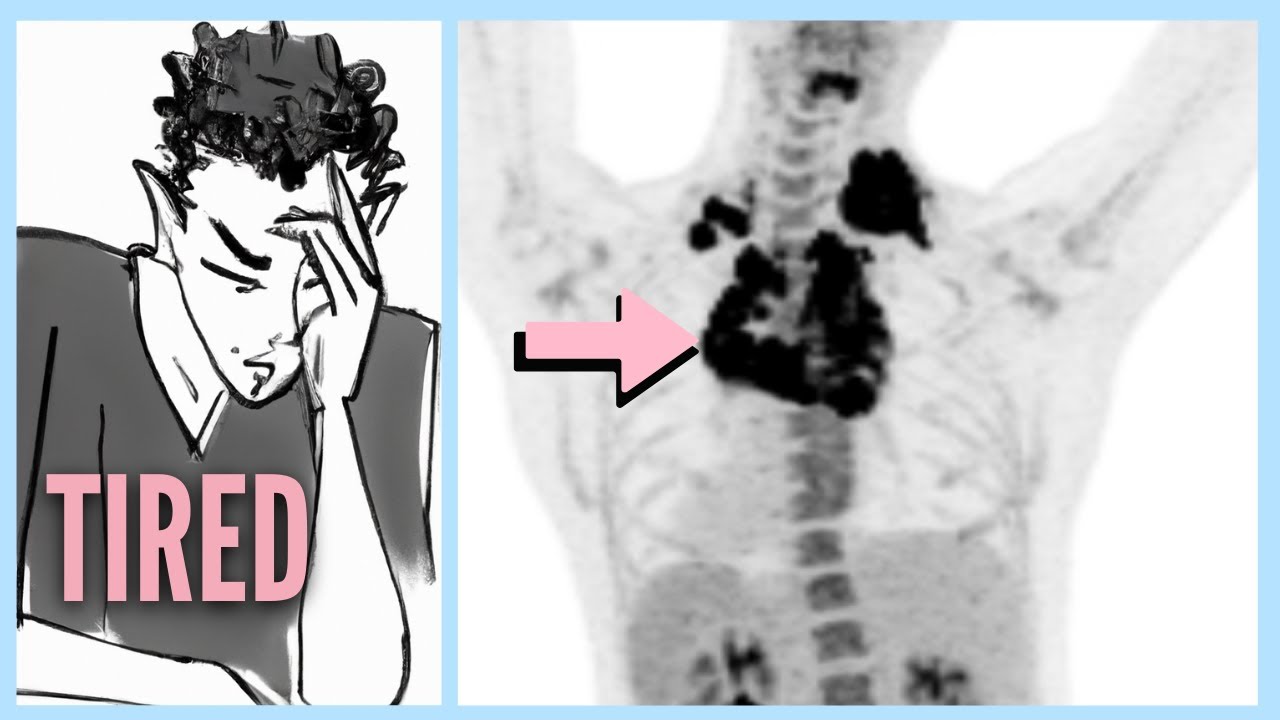

Title ID: lymphoma-after-ignoring-6-warning-signs

Original Title: Lymphoma After Ignoring 6 Warning Signs

Lymphoma After Ignoring 6 Warning Signs

Title: Lymphoma After Ignoring 6 Warning Signs